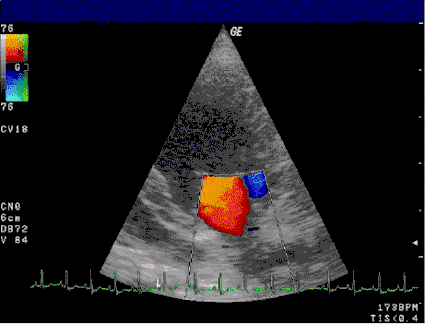

![]() Regurgitación de sangre a través de la válvula mitral, un efecto del prolapso mitral. | ||

El advenimiento del Doppler a la ecocardiografía permite ahora añadir un elemento funcional a las descripciones anatómicas del eco, el cual es útil en el diagnóstico de regurgitación mitral. El mapeo a color del flujo sanguíneo trans-mitral muestra la dirección, la velocidad y la cantidad del chorro regurgitante, si existe.[36]